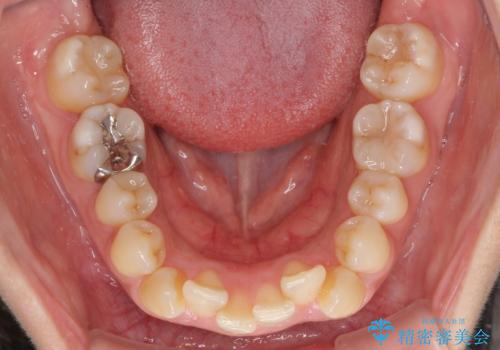

- 上下前歯のデコボコを気にして来院された患者様です。

デコボコが強いため、非抜歯で矯正をすると出っ歯仕上がりとなるため、上下左右の第一小臼歯4本を抜歯することとしました。